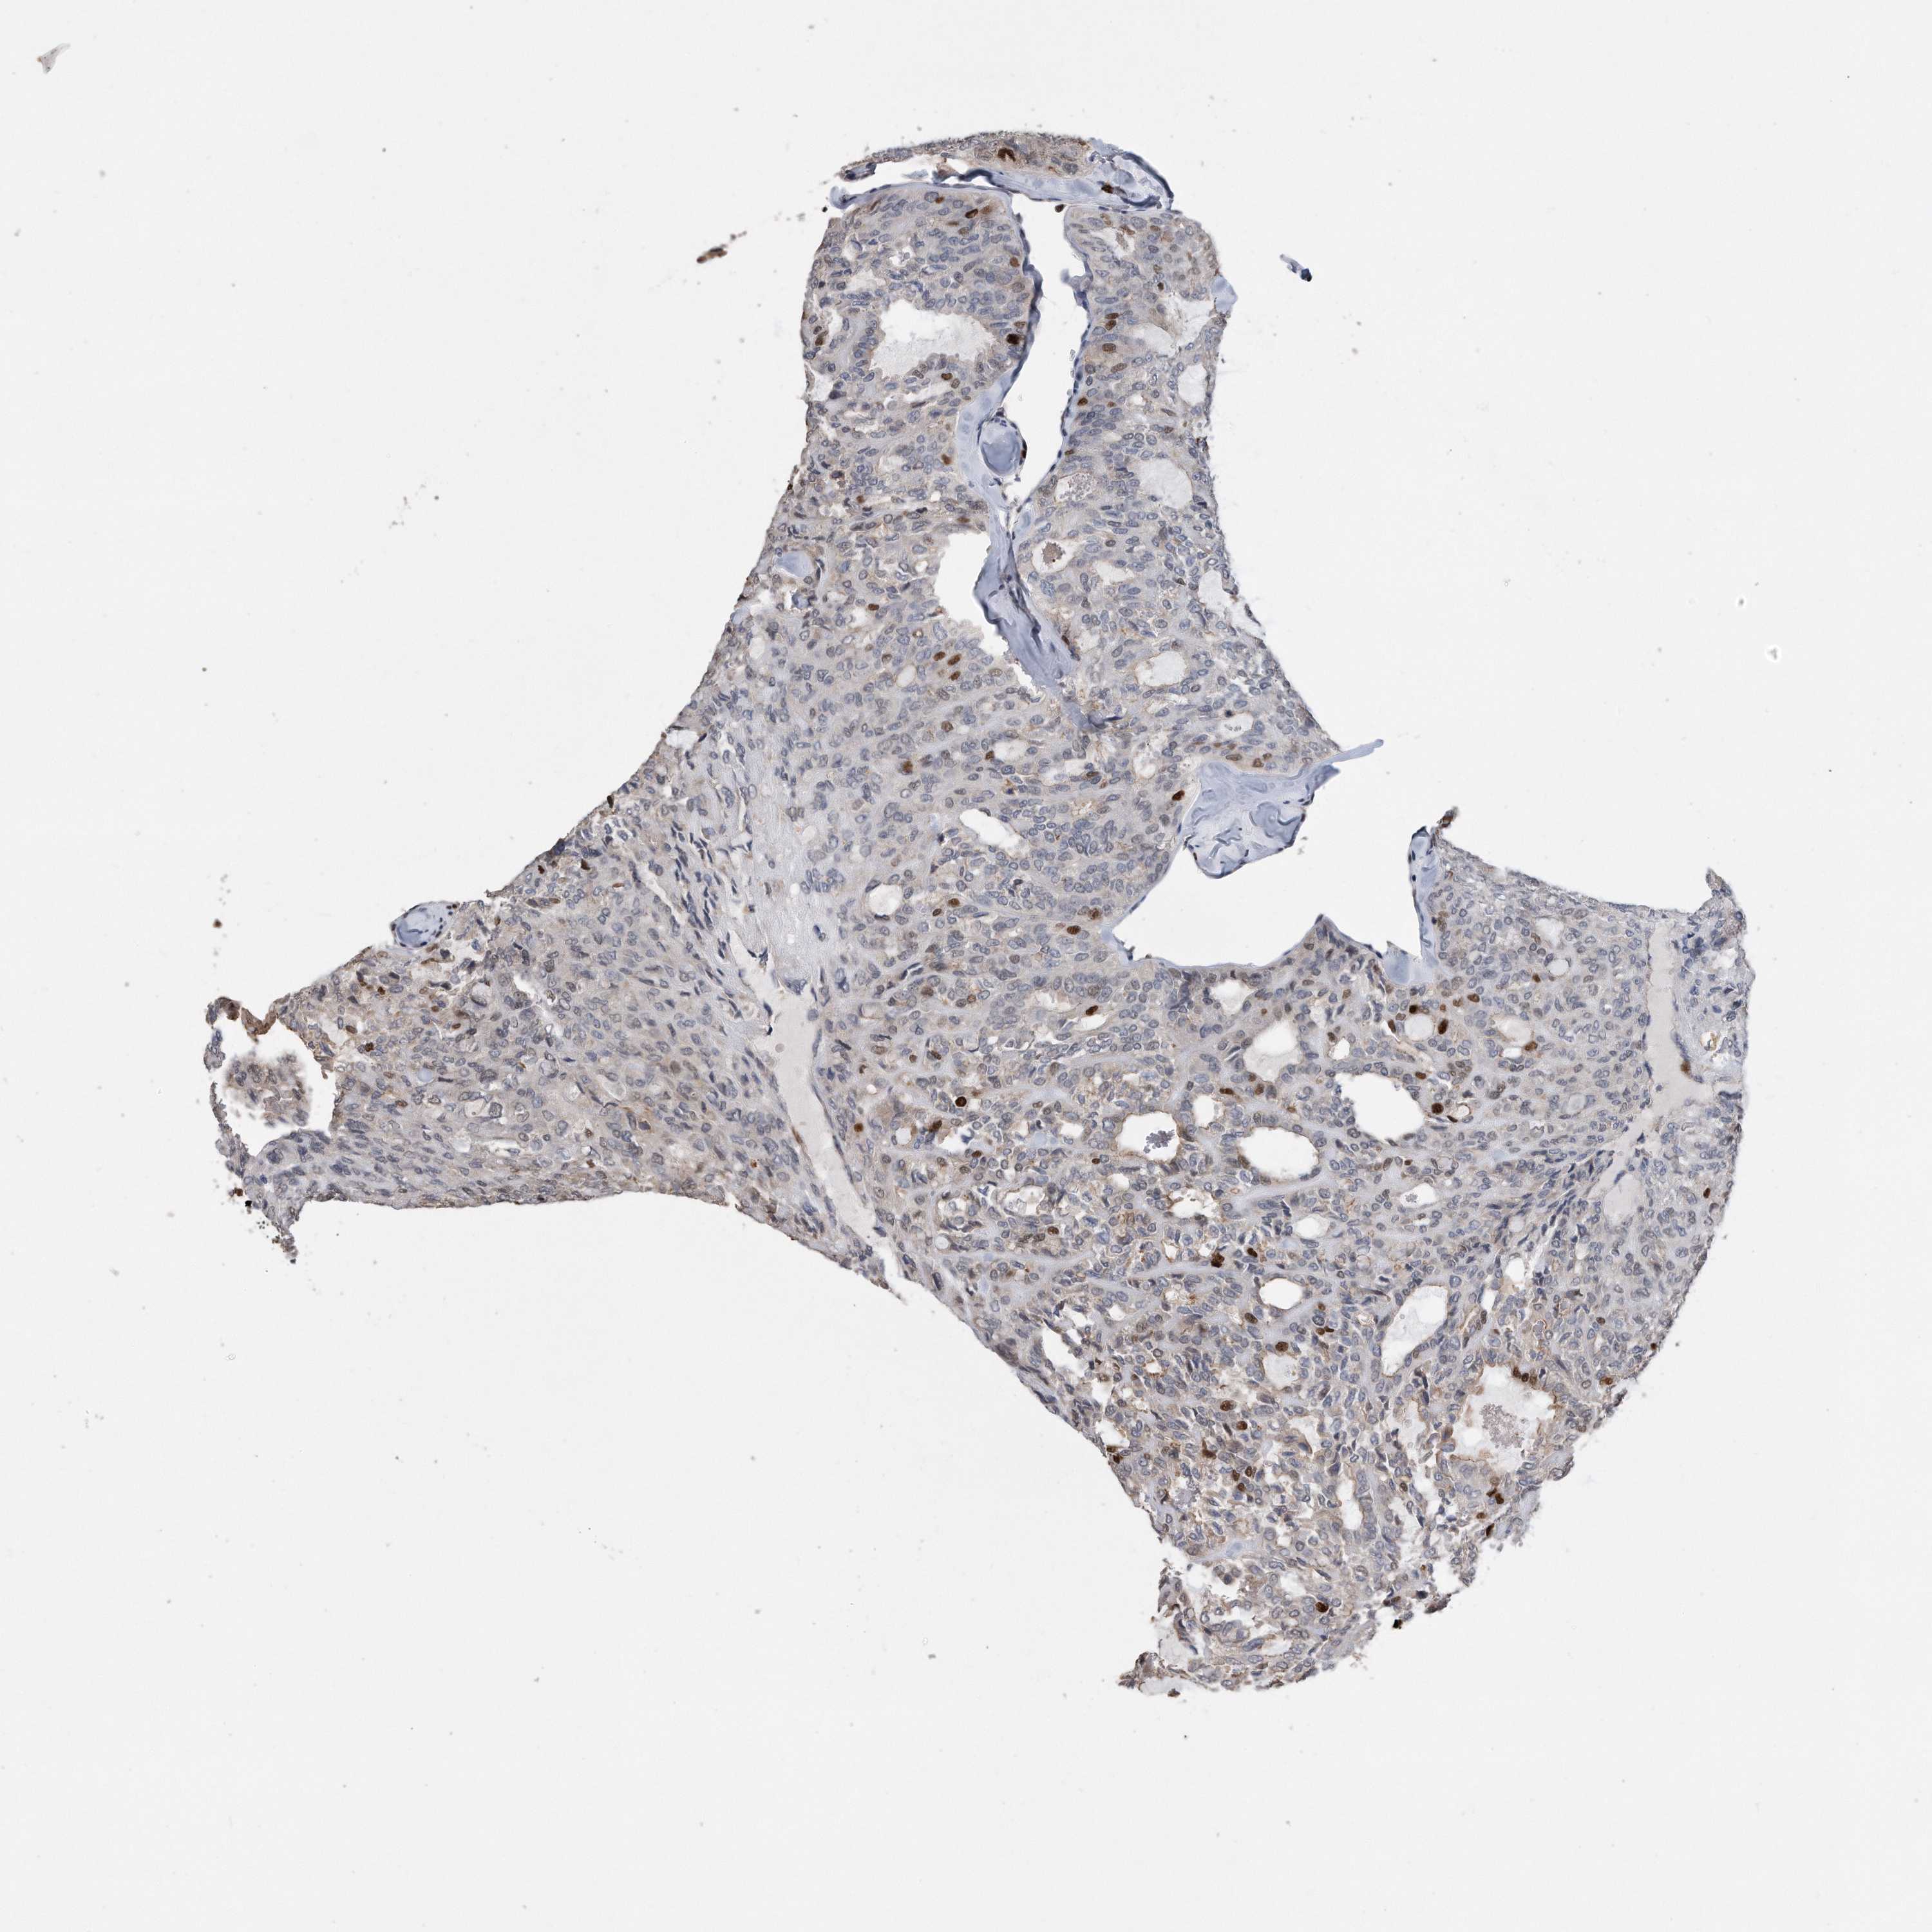

THYROID CANCER - Protein expressioni

A mouse-over function shows sample information and annotation data. Click on an image to view it in a full screen mode. Samples can be filtered based on level of antibody staining by selecting one or several of the following categories: high, medium, low and not detected. The assay and annotation is described here.

Note that samples used for immunohistochemistry by the Human Protein Atlas do not correspond to samples in the TCGA dataset.

Antibody stainingi

Antibody staining in the annotated cell types in the current human tissue is reported as not detected, low, medium, or high, based on conventional immunohistochemistry profiling in selected tissues. This score is based on the combination of the staining intensity and fraction of stained cells.

Each image is clickable and will lead to virtual microscopy that enables deeper exploration of all samples and also displays staining intensity scores, fraction scores and subcellular localization as well as patient and tissue information for each sample.

Staining

High

Medium

Low

Not detected

Intensity

Strong

Moderate

Weak

Negative

Quantity

>75%

75%-25%

<25%

None

Location

Nuclear

Cytoplasmic/membranous

Cytoplasmic/membranous,nuclear

Papillary adenocarcinoma, NOS

Follicular adenoma carcinoma, NOS

Carcinoma, NOS